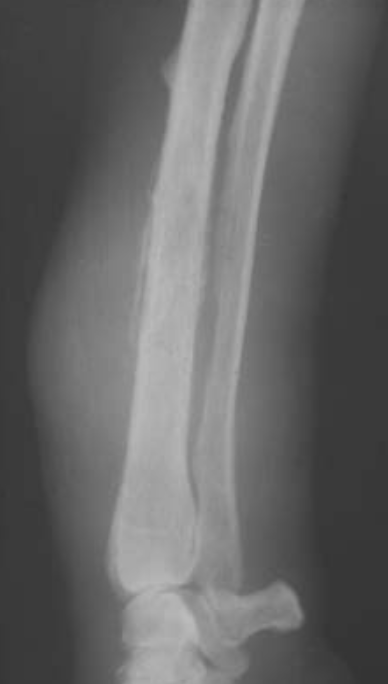

Q

Proximal tibial

osteosarcoma with amorphous bone

formation seen lateral to the proximal fibula. A solid periosteal reaction (Codman’s triangle, arrowed) is present on the lateral cortex of the proximal tibial diaphysis.